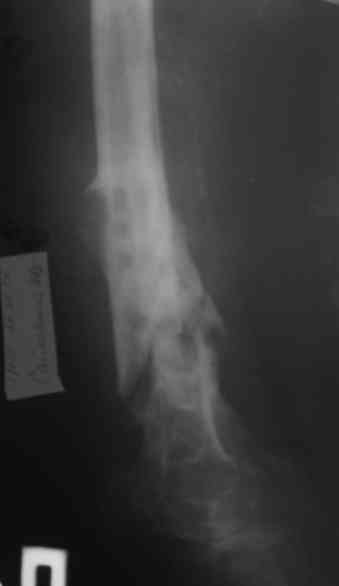

Уважаемые коллеги! Пациент лечился по поводу перелома н/3 бедра 1 год назад.

В настоящий момент: Несросшийся перелом н/3 правого бедра. Остеомиелит, свишевая форма.Контрактура коленного сустава.

Из свища скудное гнойное отделяемое. Как минимизировать количество операций, максимально улучшить качество жизни, сократить время пребывания в аппарате внешней фиксации, т.е. вернуть больного к нормальной жизни за минимальное количество ходов?

Привет. Я имел в виду предложенную Вами программу лечения. Поражение кости остеомиелитическим процессом (судя по рентгенограммам) не канальное - когда спейсер можно поставить в канал после санации на какое-то время, а по всей окружности кости - когда придется делать спейсер в виде простой "болванки на арматуре). Вероятнее всего при хорошей санации получится дефект и укорочение. При втором этапе (как я понял, вы планируете БИОС) не факт, что восстановите длину и не "полыхнет" инфекция. Поэтому и предложена другая программа. Ваше право выбора - удачи на сложном пути избавления больного от ятрогенного о\миелита. Если проинформируете, что получилось, спасибо.